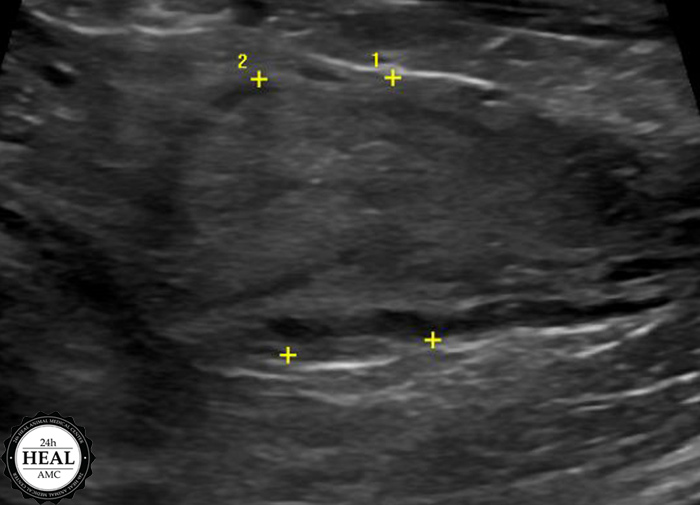

정확한 원인을 파악하기 위해 방사선, 초음파 검사를 실시했습니다.

초음파 검사 결과 미*는 자궁 내 농성이물이 의심되는 소견이 있었습니다.

추가적으로는 구토, 설사, 체중 감소, 복압 항진 등이 있습니다.고양이 자궁축농증 진단 초음파를 통해 가장 정확한 진단이 가능하며, 추가적으로는 혈액검사, 소변검사 등이 필요하였습니다.